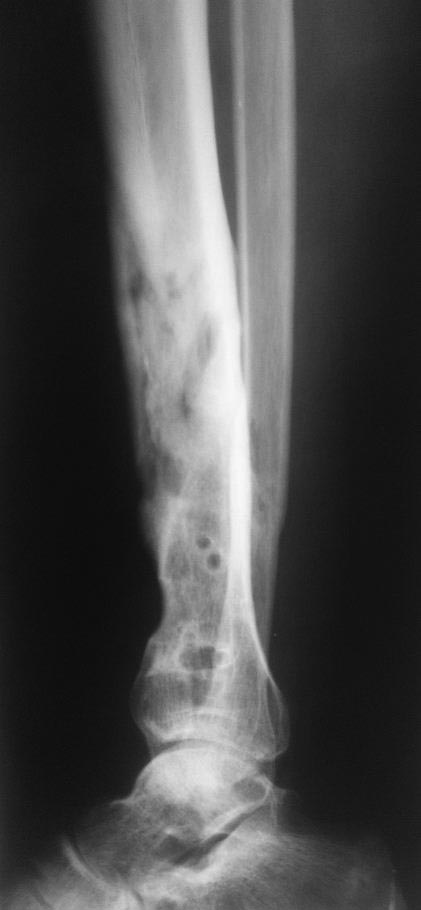

На этой неделе пациент пришел на консультацию.Рентгенограммы в приложении. Местно: отек, гиперемия кожи по передней поверхности левой голени в нижней трети, в области послеоперационного рубца - свищ, со скудным серозно-гнойным отделяемым.

Зачем же так сразу - резецировать!Уберите кольцевидный секвестр(отлично виден на прямой рентгенограмме) И наверное на этом все и закончиться, в ближайший год.Консерватизм не самое худшее качество хирурга!